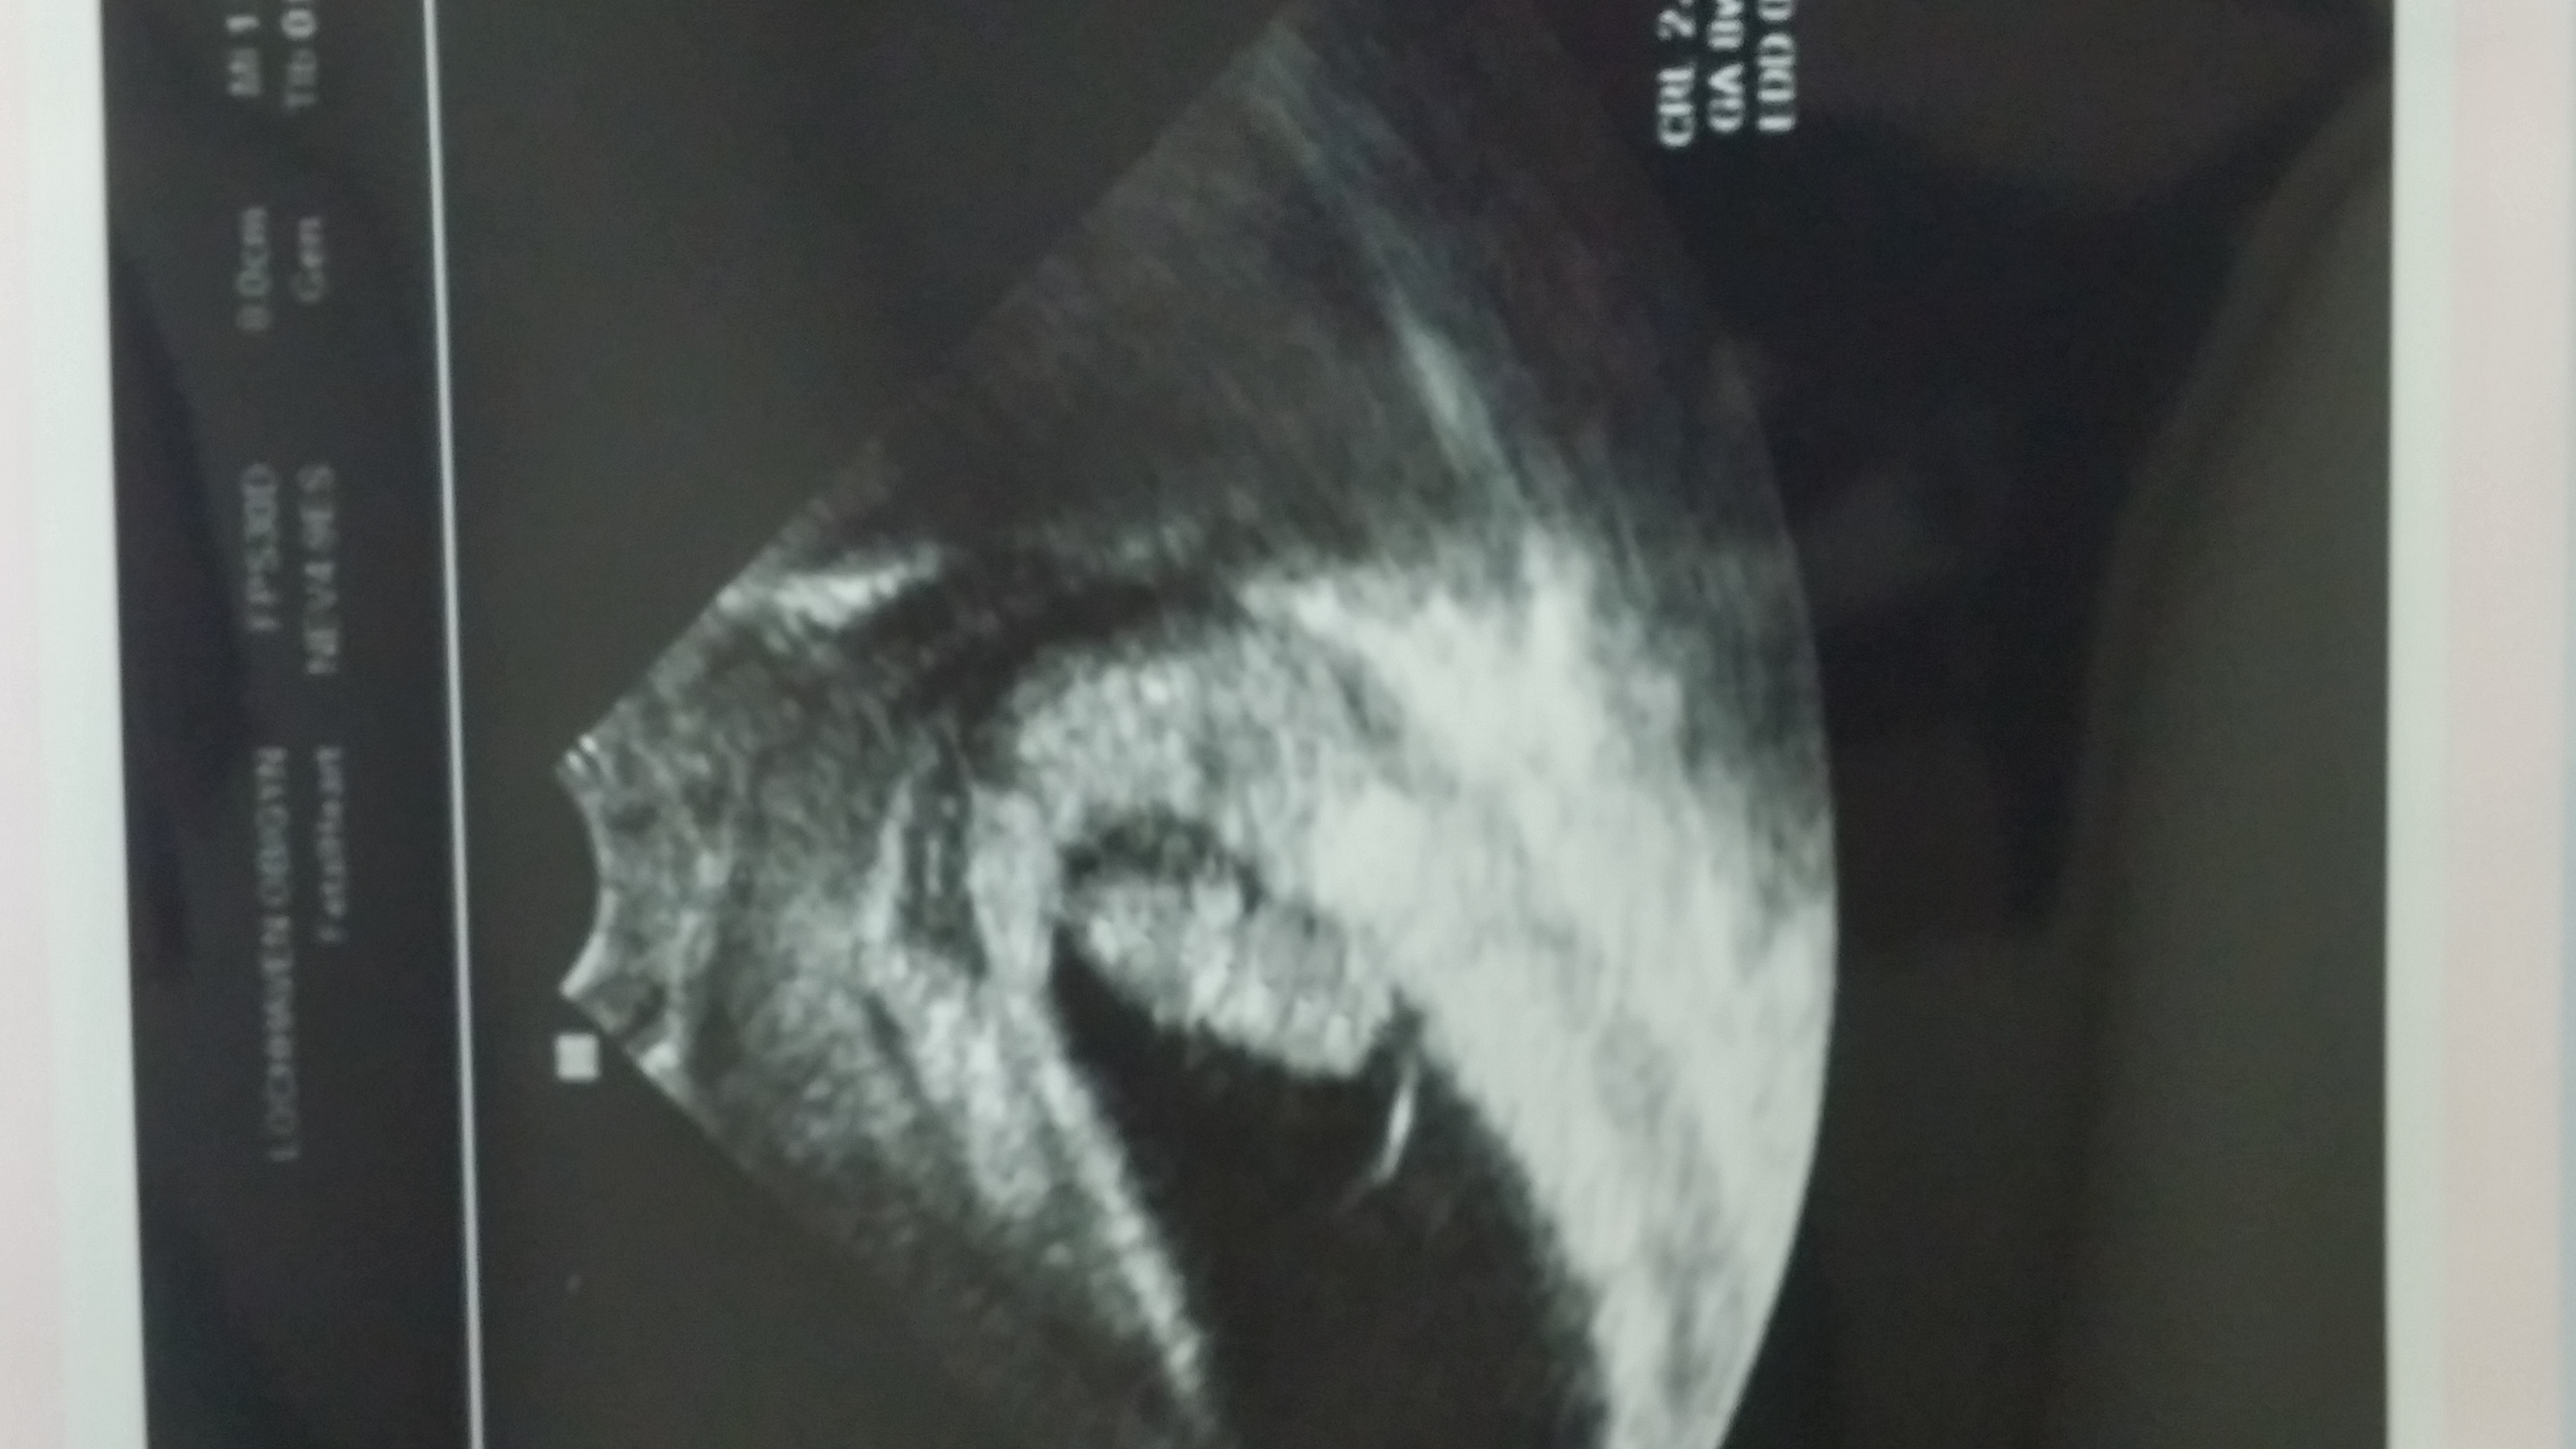

• Our almost-7week pod!

• We saw our little peanut!! We thought we were 6w6d but we measured 7w1d with a heartbeat of 131!!! We are so excited!!!